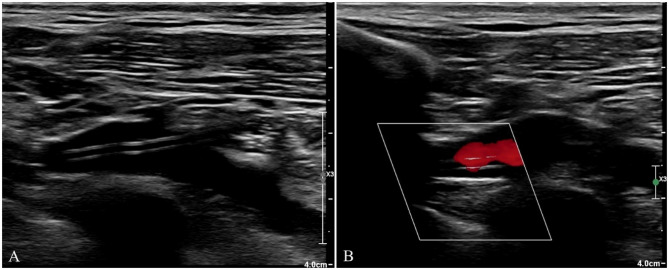

Venous Port implantation in persistent left superior vena cava with azygos vein variation: a case report and literature review.